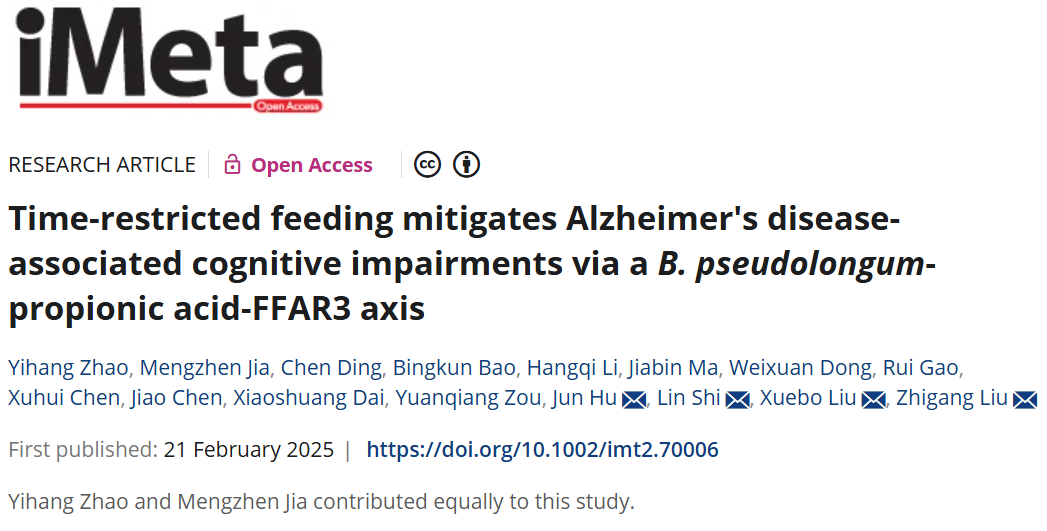

限制时间饮食通过假长双歧杆菌-丙酸-FFAR3通路减缓阿尔兹海默相关的认知功能损伤

● 本研究首次开展了时间限制饮食(TRF)对阿尔兹海默病(AD)患者的临床干预,发现TRF具有显著的神经保护作用,确定了假长双歧杆菌(B. pseudolongum)和丙酸(PA)在AD发病机制中的核心作用。

● 限制时间饮食(TRF)可改善阿尔兹海默病(AD)患者的认知功能,尤其是显著提高执行能力;

● AD小鼠的多组学整合分析发现,假长双歧杆菌(B. pseudolongum)和丙酸(PA)是TRF改善认知功能的关键靶点;

● TRF缓解AD引起的认知损伤的潜在分子机制为B. pseudolongum-PA-游离脂肪酸受体3(FFAR3)通路;

● 队列研究和TRF临床干预均表明PA是AD的潜在生物标志物。

限制时间饮食(TRF)有望缓解衰老过程中认知能力的下降,尽管通过肠脑轴的确切机制仍不清楚。在一项临床试验中,我们首次观察到四个月的TRF改善了阿尔兹海默病(AD)患者的认知障碍。在5xFAD小鼠中证实了TRF对减轻认知功能障碍、淀粉样蛋白沉积和神经炎症的肠道微生物群依赖性作用。多组学整合分析将假长双歧杆菌(B. pseudolongum)和丙酸(PA)与 AD 发病机制中的关键基因联系起来。口服补充B. pseudolongum或PA可发挥与TRF相同的神经保护作用。正电子发射断层扫描成像证实PA可穿透血脑屏障,而游离脂肪酸受体3(FFAR3)的敲低削弱了TRF的认知益处。值得注意的是,我们观察到粪便中PA的含量与AD患者认知状态之间呈显著正相关,这进一步表明TRF促进了PA的产生。这些发现强调了微生物群-代谢物-脑轴是TRF发挥认知益处的关键,表明B. pseudolongum或PA是潜在的AD治疗的关键靶点。

本研究通过系统性调查,深入探讨了TRF在改善AD相关认知障碍方面的治疗潜力。首次发现,4个月的TRF干预显著改善了AD患者的认知状态;3个月的TRF可有效延缓转基因AD模型小鼠(5xFAD小鼠)的病理进展,该模型能够快速重现AD的淀粉样蛋白病理特征。多组学整合分析及随后的抗生素干预实验进一步证明了肠道菌群-代谢物-脑轴在TRF对AD小鼠认知功能改善中的关键作用。此外,研究发现,TRF可显著促进益生菌假长双歧杆菌(B. pseudolongum)在AD小鼠肠道的定植,而该菌种能够通过产生丙酸(PA)特异性激活游离脂肪酸受体3(free fatty acid receptor 3, FFAR3),从而模拟TRF对AD相关认知障碍的改善作用。横断面人群研究及TRF临床干预试验均进一步证实,认知功能与粪便PA水平之间存在显著关联。本研究明确且有力地证明了肠道微生物群及其代谢产物在TRF与AD生理病理过程中的关键联系,并进一步揭示了B. pseudolongum或PA作为AD营养干预治疗的潜在应用价值。